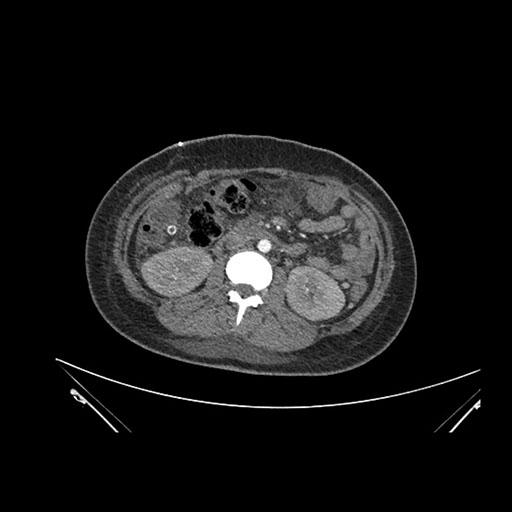

Axial Arterial